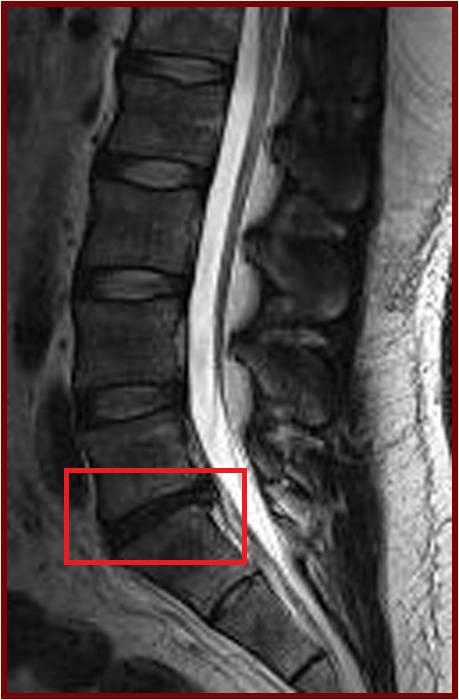

世界各地人口都受腰痛影響,而腰痛亦是為香港勞動人口造成不健康及病假的主要原因。導致腰痛的其中一個主要原因是脊椎的關節,即椎間盤出現退化。香港大學李嘉誠醫學院矯形及創傷外科學系一項研究發現,肥胖的成年人出現椎間盤退化及發展成更嚴重的病徵的機會,較正常體重的成年人高一倍。是次研究內容是值得大眾關注的健康課題,其研究結果已刊登於最新一期的權威醫學期刊《Arthritis and Rheumatism》。

今次的研究是一項以南中國地區人口而作出的具代表性抽樣研究,從上述大型人口群組中抽出21歲或以上的成年人為研究對象。在是次的研究中,研究人員分析了合共2,599位成年人的磁力共振(MRI)檢查數據。當中27%(709人)沒有椎間盤退化,而73%(1,809人)則有椎間盤退化。在患有椎間盤退化的成年人當中,有7%體重過輕,48%體重正常,36%過重和9%肥胖。超重及肥胖的成年人出現椎間盤退化程度及發展成更嚴重的病徵的機會,比正常體重或過輕的成年人嚴重。